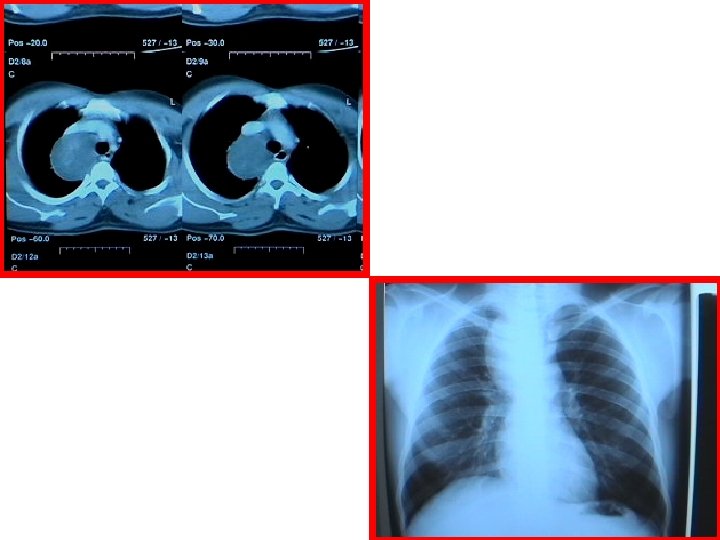

B. Bronchiectasis Def. Bronchial dilatation Cause § Congenital ( systic fibrosis, immotile ciliac syndrome = kartignar syndrome) § Infection ﻳﺴﻮﻱ ﺃﻮﺑﺴﺘﺮﻛﺸﻦ § Obstruction ( chronic : tumour if it is slow growing others: foriegn body , infection , diseases Of childhood : measels, whooping cough ) Clinical Features § Cough ( morning with sputum ) <<make sure § Dyspnea § Haemoptysis (50%) § Clubbing Types : • • Cystic Cylindrical (usually widespread through a bronchial tract)

Investigation § Bronchogram ( invasive : catheter & contrast ) § CT § Bronchoscopy Treatment § Medical ‒ Resolve most cases ( perfused , bilateral , cylindrical ) § Surgical (Indications) ‒ ‒ Failure of medical Rx cystic dilatation not cylinderical Patient with localized disease ( )ﻗﺴﻢ ﻭﺍﺣﺪ ﻣﻦ ﺍﻟﺮﺋﺔ , Not perfused ( doesn’t have arteries for perfusion. . How to know ? By : VQ scan ) P. S : most of the cystic are not perfused ; )

Indications for surgery in this case of Left Lower Bronchiectasis ‒ ‒ ‒ cystic dilatation. localized Not perfused ( by VQ scan )